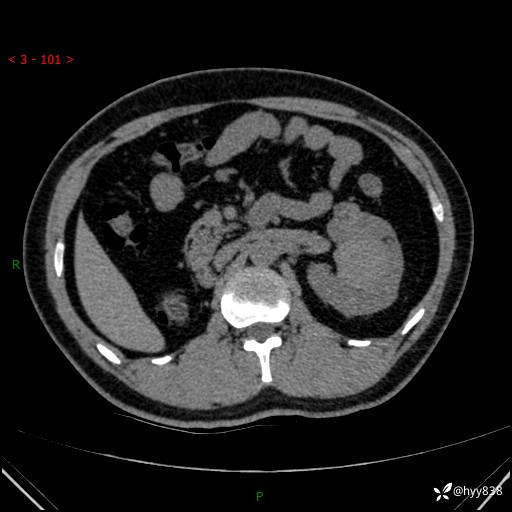

患者性别:男

患者年龄:28岁

简要病史:右肾肿瘤术后,常规复查

辅助检查:CT

临床诊断:右肾肿瘤术后

腹部CT+颅脑CT平扫